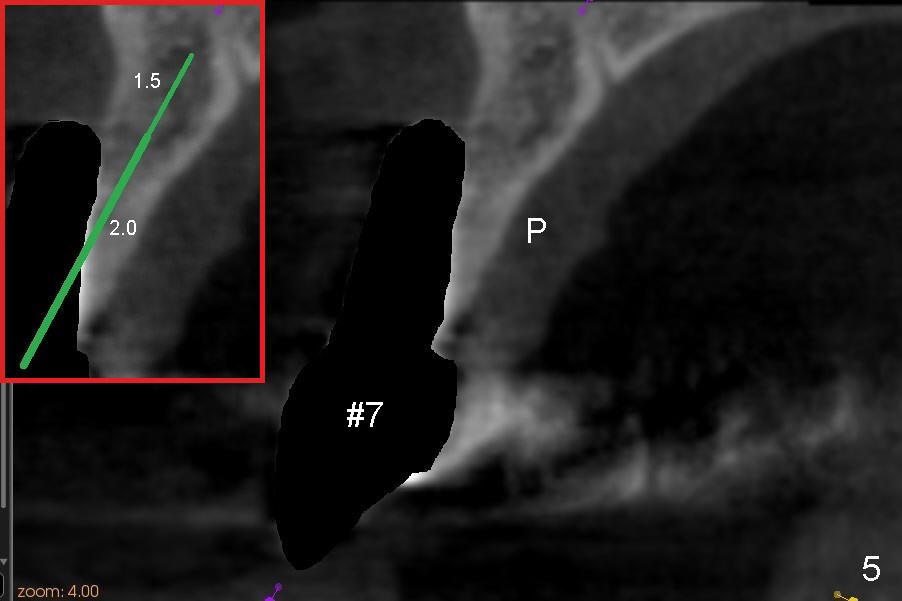

Finally the displaced implant is exfoliated itself, leaving a crater (Fig.1 arrowheads). CBCT shows the knife-edged ridge post exfoliation of the implant at the site of #7 (Fig.5, as compared to that prior to exfoliation). After using 1.5 mm pilot drill at 17 mm and 2.0 mm at 14 mm (Fig.5 insert), a 3.0x17 mm one piece angled (15 º) implant is placed (Fig.2, 10). Palatal view reveals that the implant is placed buccally (Fig.3); ideally the implant should be more palatal (Fig.3 insert: circle). Please take postop CBCT to confirm the placement. The buccal placement is partially related to the elongated tooth (Fig.4).